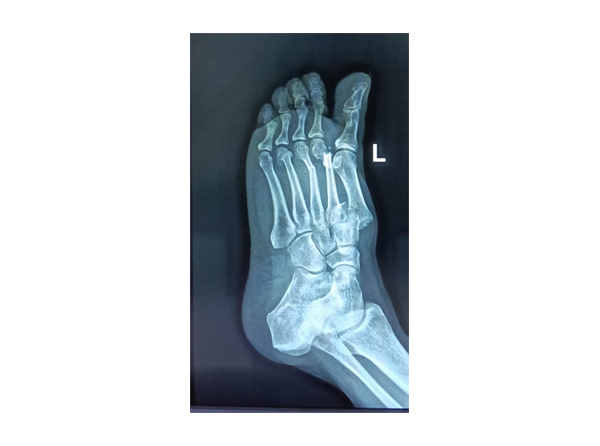

Sports Injury

Sports injuries are injuries that occur during exercise, physical acti